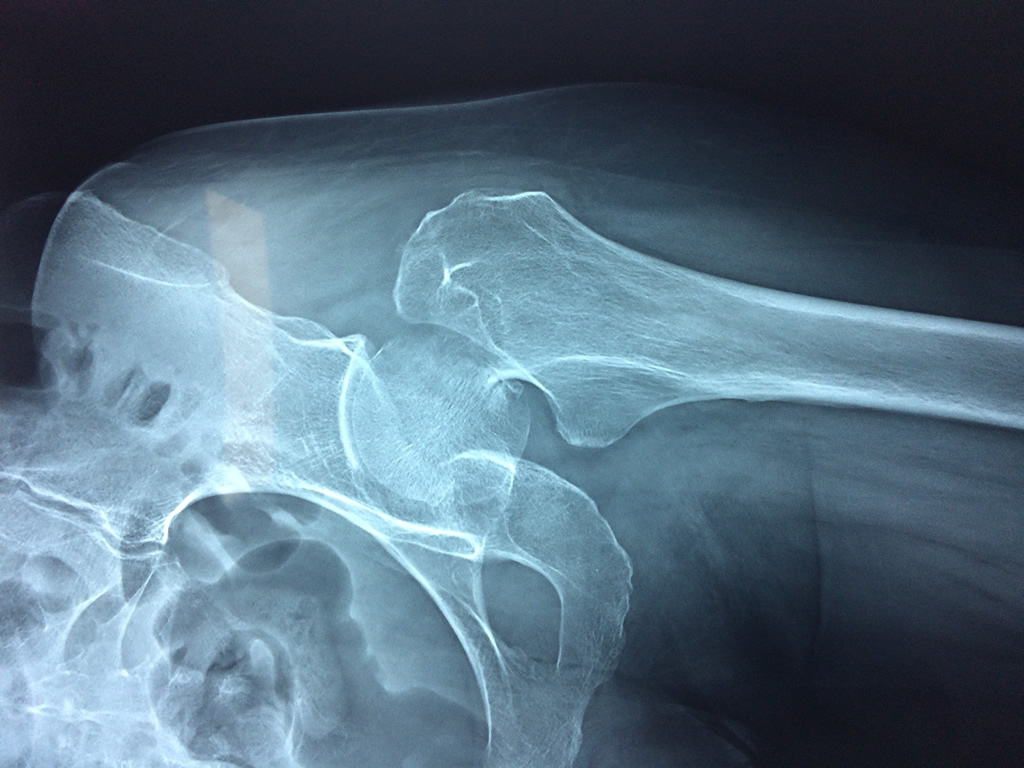

Fémur - Cadera

La cirugía de fractura de cadera se realiza para reparar una ruptura en la parte superior del hueso del muslo. Este hueso se denomina fémur.

Es parte de la articulación coxofemoral. Si una fractura de cadera no recibe tratamiento, es posible que deba permanecer en una silla o en la cama.